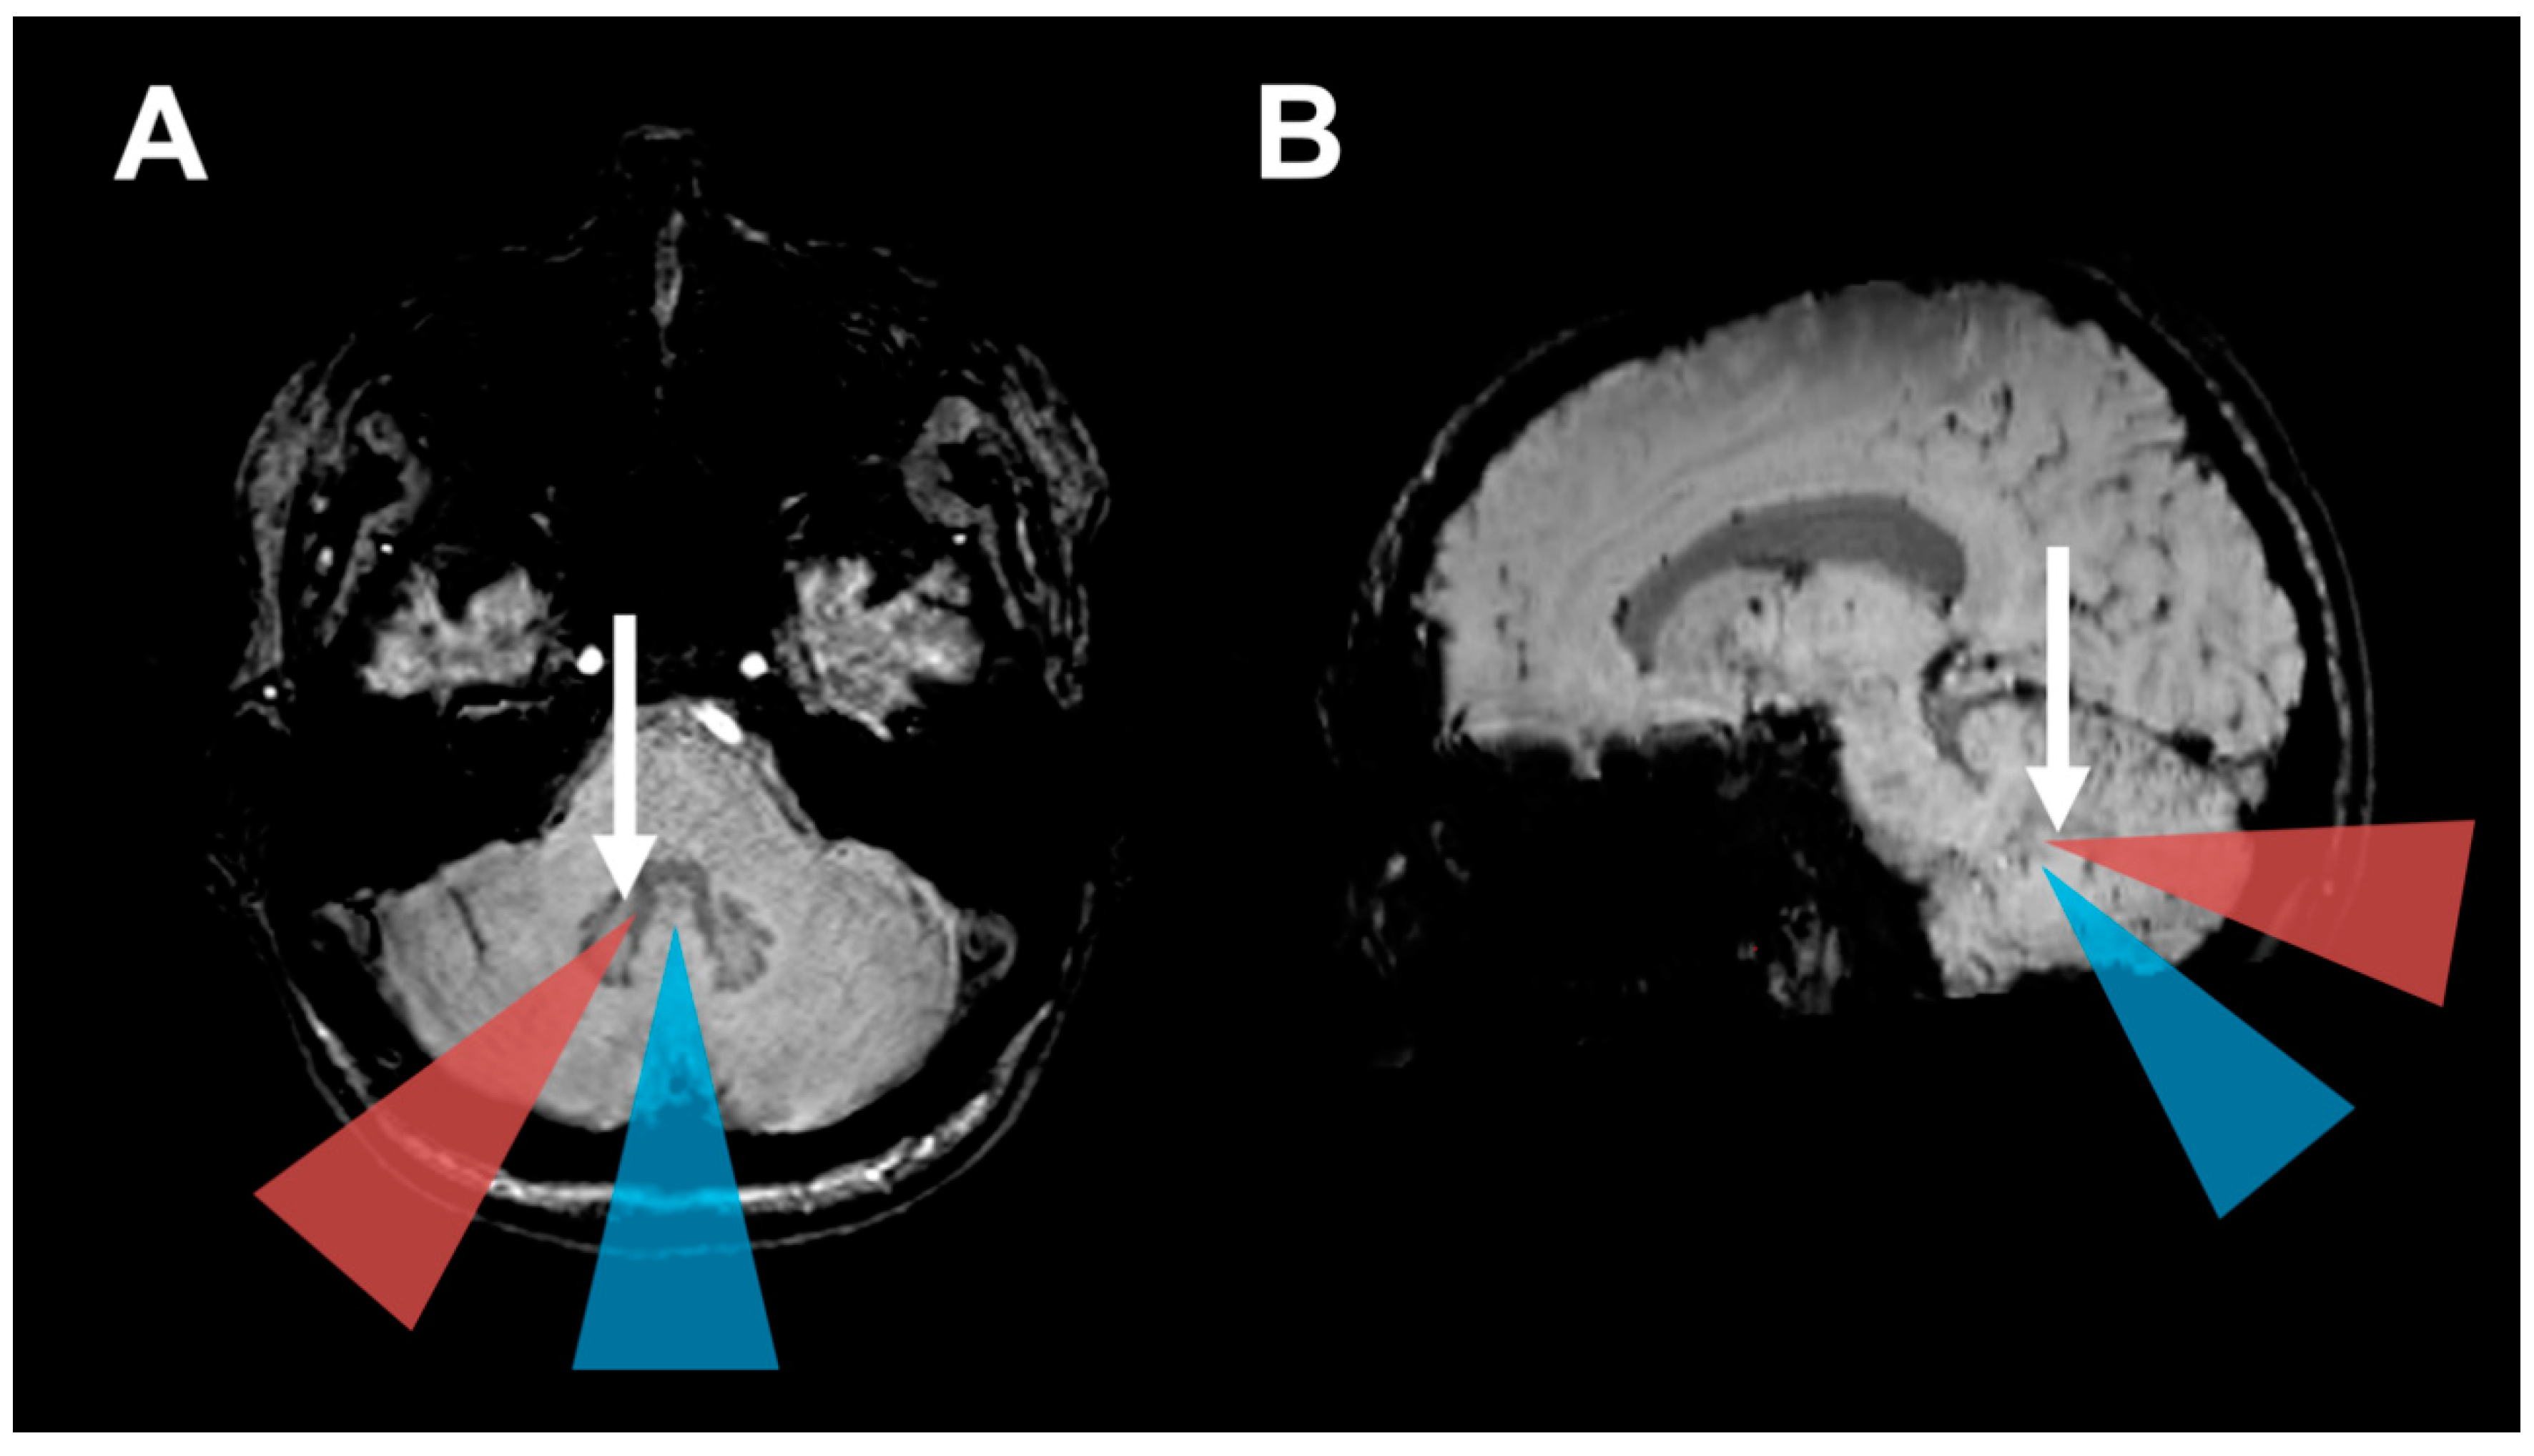

Figure 3.

HOD development based on operative approach: (A) Axial and (B) parasagittal magnetic resonance susceptibility-weighted images (SWI) illustrate the operative approaches investigated in this study. The blue triangles indicate midline approaches (telovelar and transvermian). The orange triangles indicate the paravermal trans-cerebellar operative corridor that frequently led to hypertrophic olivary degeneration in our cohort by injury to the dentate nucleus (Arrows).

In clinical routine, patients with posterior fossa tumors present with increased intracranial pressure and focal neurological deficits secondary to compression of the brainstem, cranial nerves or cerebellar tissue [41]. Furthermore, due to the tumor anatomy identifying DN is often complicated. Therefore, postoperative outcome parameters comprise of the immediate improvement of these symptoms derived mostly from the reduction of tumor mass effect. In contrast, the symptoms of HOD begin with a delay of months, progress slowly and are easily missed, complicating the allocation to the disease [5]. In concordance with literature, this study found the HOD on MRI with a delay of four months (median) after the contralateral surgical lesion [5,6,7]. Furthermore, most patients are usually not examined clinically in such a depth by neurosurgeons, so that the HOD symptoms may be missed. Some patients with HOD may thus be overlooked in clinical routine and the novel symptoms may mistakenly be attributed to tumor growth or novel pathology [5]. Impedingly, the clinical syndrome and especially palatal tremor is seldom diagnosed. Postoperative speech pathologist exam including fiberoptic endoscopic evaluation of swallowing (FEES) is considered a gold standard for detecting palatal tremor, but regular implementation is not yet universal amongst hospitals [14]. Furthermore, radiologists should also be sensitized for the imaging hallmarks of HOD. For a reliable detection of HOD, axial T2-weighted or FLAIR sequences with a slice thickness of at most 4 mm is recommendable. On standard MR-sequences such as T1-weighted imaging, preoperative identification of the DN can be challenging. However, in our experience the DN can be very well localized on susceptibility weighted imaging (SWI), which we therefore recommend for the neurosurgical planning (see Figure 3). In summary, since the HOD may be associated with a disabling clinical syndrome and therapeutic options are still unavailable, it must be primarily prevented [9,11,13]. Neurosurgeons therefore should consider sparing the DN in the surgical trajectory to prevent HOD occurrence whenever feasible. In some patients another operative trajectory is possible, whereas in other patients a fissure dissecting approach instead of a trans-cerebellar approach should be considered.